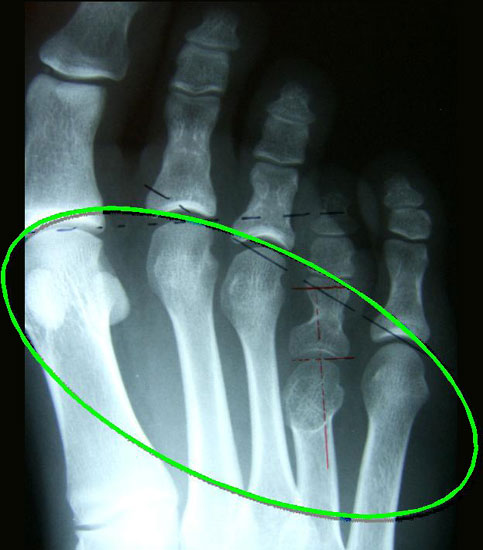

• Röntgenaufnahmen beider Füße a.p. und streng seitlich unter Belastung sowie Schrägaufnahme beider Füße ohne Belastung.

• Ausmessen der zu verlängernden Strecke des betroffenen Metatarsale und damit Beurteilung der Defektstrecke zur Rekonstruktion des Metatarsaleindex.

Der Autor überblickt 73 Rekonstruktionen der Brachymetatarsie mittels internem Distraktor und über 19 Verlängerungen von Metacarpalia oder Fingerphalangen bei posttraumatischen Deformitäten oder angeborenen Reduktionsdefekten bzw.  Aplasien.

Meist kam ein 18mm Minifixateur zur Anwendung und ausnahmslos wurde er lateral am Metatarsale implantiert. Bis auf das Metatarsale 5 wurden vom Autor alle weiteren Metatarsalia (MT1 – MT4) isoliert oder kombiniert verlängert. In 7 Fällen wurde eine simultane Verlängerung zweier Metatarsalia (2x MT1 und MT4, 4x MT3 und MT4, 1x MT2 und MT3) vorgenommen. Bei einem Großteil der Patienten musste eine Strecksehnenverlängerung entweder im Rahmen der Erstoperation oder im Rahmen der Aktivatorentkopplung vorgenommen werden. In neun Fällen (ausnahmslos bei Erwachsenen > 30 Jahre) sogar 2x sowohl während des Erst- als auch Zweiteingriffes. Annähernd regelhaft sind bei den eben genannten Eingriffen Arthrolysen des Metatarsophalangealgelenks des betroffenen Zehenstrahls erforderlich, da durch die Distraktionsverlängerung eine hohe Kompression auf das jeweilige Grundgelenk entsteht.